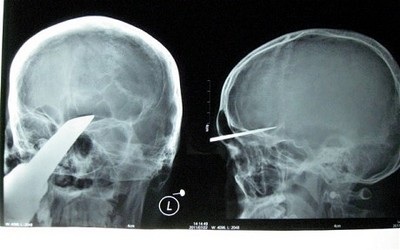

Phim chụp X-Quang cho thấy thanh kiếm cắm sâu trong đầu nạn nhân.